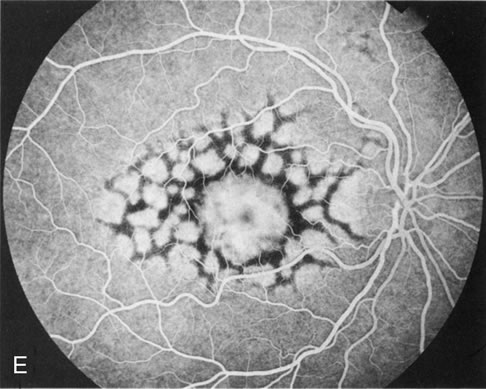

Fig. 13. Hereditary hemorrhagic macular dystrophy (pseudoinflammatory macular dystrophy of Sorsby). Fluorescein angiography in this family member demonstrates that the earliest finding is an isolated choroidal neovascular membrane B). Despite laser photocoagulation, a hemorrhagic maculopathy developed in this eye (C, D) and eventually a disciform scar (E) formed, as it had in the fellow eye, and in the eyes of other affected family members.

Abnormal choroidal perfusion, manifested on FA as a delay in choriocapillaris filling, has been seen in the restudy of some of Sorsby's initial pedigrees.26 This unusual pattern has been related to the histopathologic finding of a “confluent, lipid-containing, amorphous deposit found between the basement membrane of the RPE and the inner collagenous layer of Bruch's membrane.”27